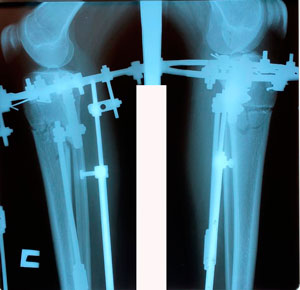

перед крутками

Вложения

image-23-03-20-12-25.jpg